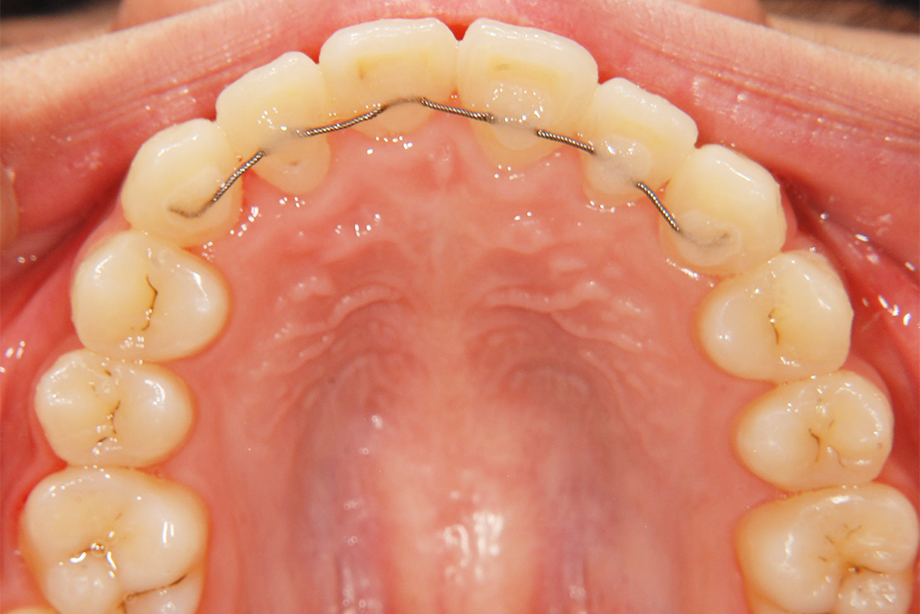

第Ⅰ期治療

乳歯、もしくは乳歯と永久歯が混ざっている時期の治療です。歯の治療というよりも、顎の骨の成長を促したり、歯並びに影響を与える筋機能の訓練などを行います。

- 矯正後